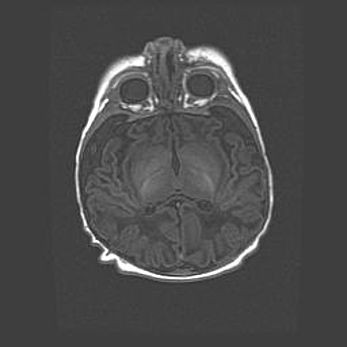

Наружная гидроцефалия с возможной атрофией височных областей.

Возраст: 28 дней

Вес: 3670 г

Пол: мужской

Окружность головы: 38 см

Срок гестации: 40 недель

Гидроцефалия головного мозга у новорожденных – это заболевание, которое характеризуется скоплением избыточного количества спинномозговой жидкости в желудочковой системе головного мозга в результате затруднения её перемещения от места выработки к месту поглощения в кровеносную систему или вследствие нарушения абсорбции. При открытой наружной форме гидроцефалии у новорожденных расширяются и переполняются субарахноидные пространства.

При нормотензивных  формах,  которые,  как  правило,  являются  следствием  перенесенных ишемических  повреждений  паренхимы  мозга,  возможно  сочетание микроцефалии  с нормотензивной гидроцефалией. В основе данных изменений лежит атрофия больших полушарий с преимущественной  локализацией  в  лобно-височных  областях.